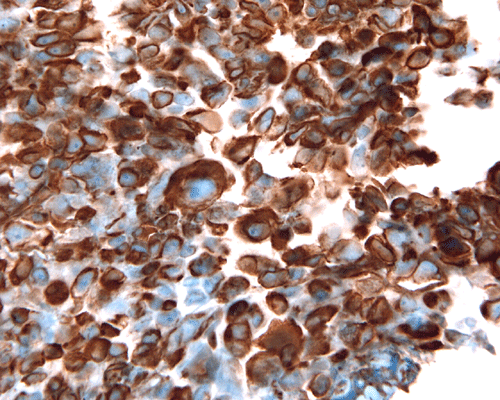

Immunohistochemistry, the defining diagnostic staining is loss of INI1 nuclear immunoreactivity in the tumor cells. The classic rhabdoid cells are also strongly and uniformly positive for vimentin. In fact, immunohistochemistry for vimentin is helpful in identifying rhabdoid cells. Other than vimentin, a long list of antigens is variably detected in rhabdoid tumors reflecting the polyphenotypic nature of these tumors. Epithelial membrane antigen (EMA) is detected in the rhabdoid cells and epithelial components. About half of the cases are positive for smooth muscle actin. Expression of these two antigens are rather unusual for other tumors of the central nervous system. S-100 protein is variably detectable among different cases. Intermediate filaments including neurofilament, glial fibrillary filaments, and cytokeratin are detectable in many cases. Synaptophysin is detectable particularly when a medulloblastoma-like component is present. Placental alkaline phosphatase (PLAP) and beta-human chorionic gonadotrophin (hCG) are not detectable but alpha fetal protein (αFP) can be demonstrated in some cases [Rorke LB et al., 1996; Burger PC et al., 1996].